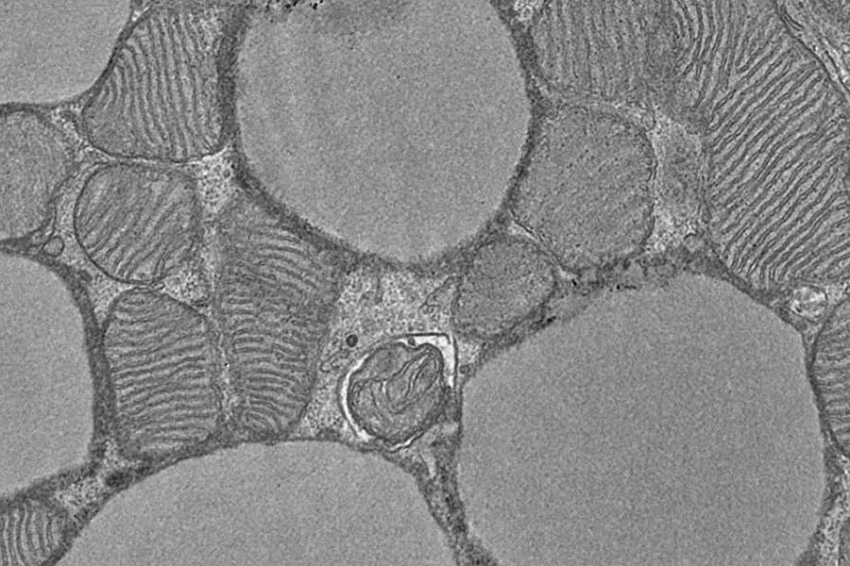

Группа ученых из Эдинбургского университета в Шотландии сделала интересное открытие в области метаболизма и генетики. Их исследование, опубликованное в журнале Nature Communications, раскрывает новые аспекты функционирования бурой жировой ткани и ее роли в процессе сжигания калорий.

Центральным объектом изучения стал ген PHD2, который в значительных количествах присутствует в бурой жировой ткани. Этот тип жировой ткани играет ключевую роль в терморегуляции организма, особенно в условиях низких температур. Бурый жир обладает уникальной способностью расщеплять молекулы сахара в крови и собственные клетки для поддержания оптимальной температуры тела.

Исследователи обнаружили, что PHD2 выполняет функцию своеобразного датчика кислорода в организме и существенно влияет на активность бурого жира. Особенно интересным оказался тот факт, что в высокогорных районах, где концентрация кислорода в воздухе ниже, процесс сжигания калорий бурым жиром протекает особенно интенсивно.

В ходе эксперимента ученые удалили ген PHD2 из бурой жировой ткани лабораторных мышей. Результаты оказались впечатляющими: организм животных начал вести себя так, будто находится в условиях высокогорья с пониженным содержанием кислорода. Примечательно, что этот эффект наблюдался даже при комфортной температуре окружающей среды, когда бурый жир обычно неактивен.

Эксперимент показал, что мыши без гена PHD2, несмотря на увеличенное потребление пищи, сжигали на 60% больше калорий по сравнению с контрольной группой. При этом у них не наблюдалось негативных последствий для обмена веществ, которые обычно сопутствуют избыточному весу.